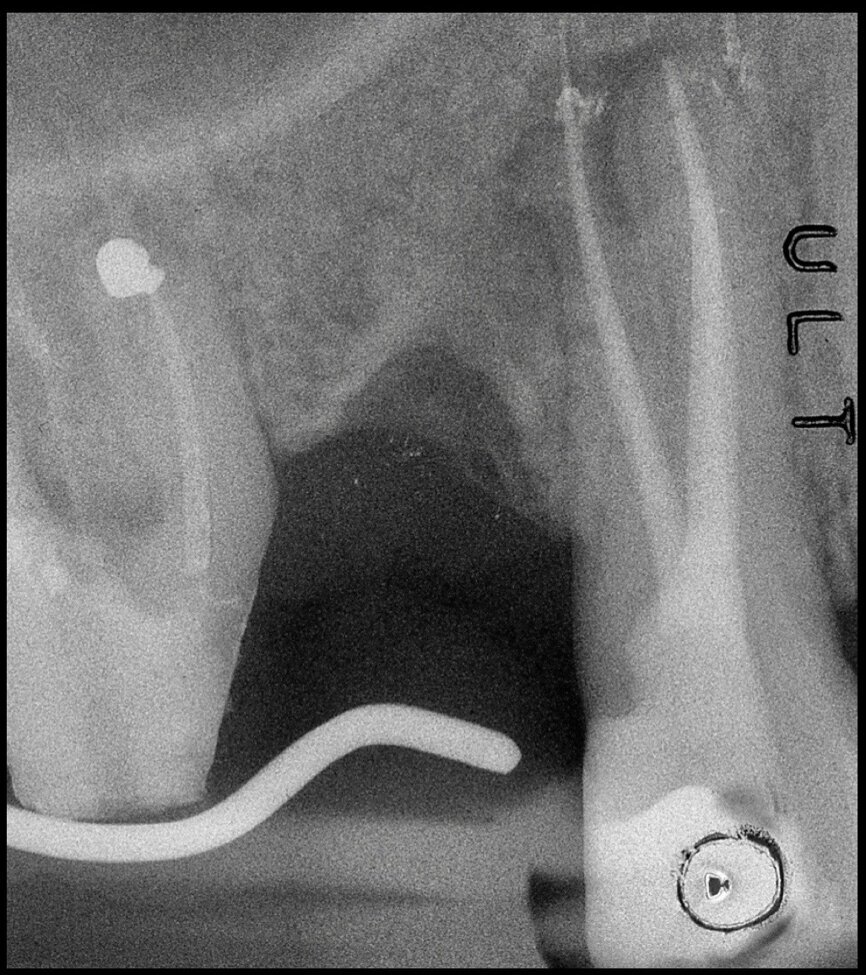

In the maxillary premolar shown in Figures 5 and 6, the fistulogram revealed the presence of an apical lesion that extended coronally to approximately the middle third of the root. The clinical decision could, therefore, propend towards orthograde retreatment; however, CBCT gave us a very different view of the situation compared with the radiograph, as it indicated that a prior treatment had irreversibly damaged the tooth, which would therefore have to be extracted.